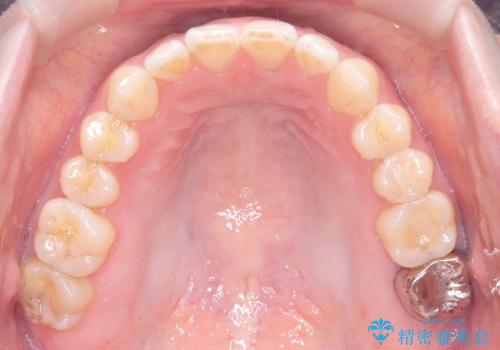

すきっ歯・切端咬合・空隙歯列|インビザラインで11ヵ月で治療完了

- すきっ歯と切端咬合(上下の前歯が先端で当たるかみ合わせ)を主訴にご来院された患者様です。

矯正検査を行った結果、非抜歯でインビザラインによる治療が可能と判断し、マウスピース矯正で改善を行いました。

11ヵ月で矯正治療が終了し、前歯の隙間も改善、見た目とかみ合わせも良好な状態となり、患者様にも大変ご満足いただけました。